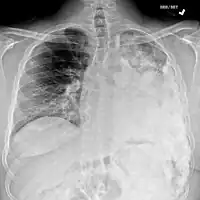

Most times, the early signs of osteosarcoma are caught on X-rays taken during routine dental check-ups. Osteosarcoma frequently develops in the mandible (lower jaw); accordingly, dentists are trained to look for signs that may suggest osteosarcoma. Even though radiographic findings for this cancer vary greatly, one usually sees a symmetrical widening of the periodontal ligament space. If the dentist has reason to suspects osteosarcoma or another underlying disorder, he or she would refer the person to an Oral & Maxillofacial surgeon for biopsy. A biopsy of suspected osteosarcoma outside of the facial region should be performed by a qualified orthopedic oncologist. The American Cancer Society states: "Probably in no other cancer is it as important to perform this procedure properly. An improperly performed biopsy may make it difficult to save the affected limb from amputation." It may also metastasise to the lungs, mainly appearing on the chest X-ray as solitary or multiple round nodules most common at the lower regions.

Metastatic osteosarcoma to the left chest